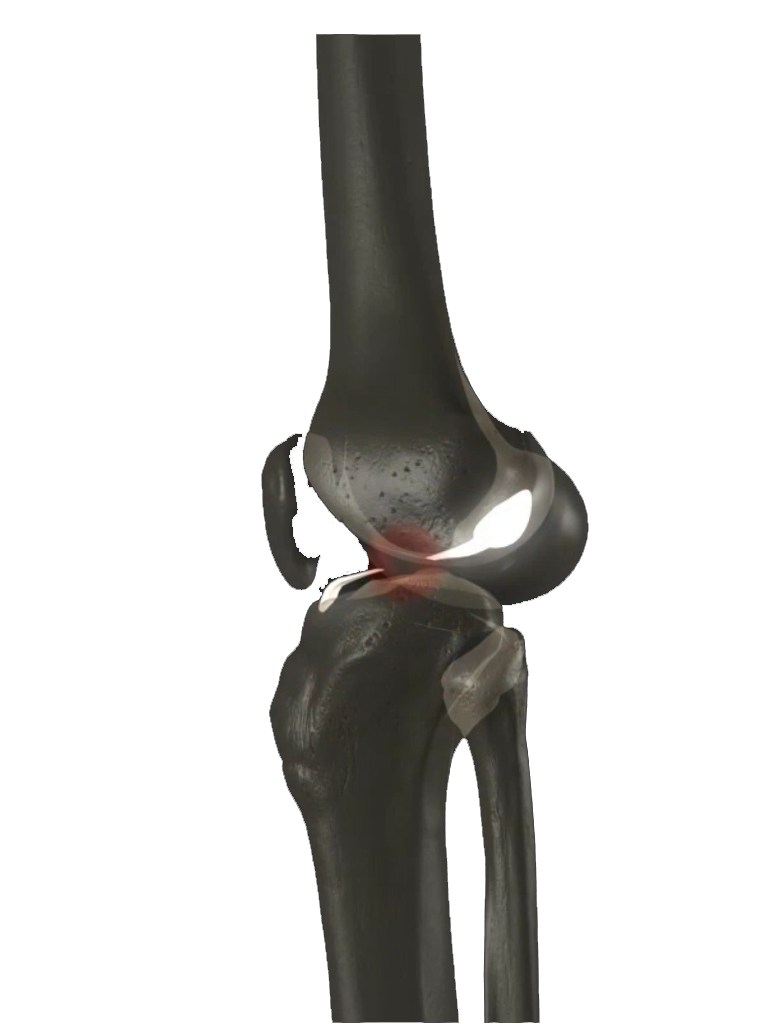

La mayor parte de las lesiones de ligamento cruzado anterior (LCA) ocurren durante la práctica de algún deporte que requiera pivoteo, cambios de dirección, o rotación de rodilla. Los síntomas de una lesión de LCA pueden variar, desde sentir que "se va" o sale de control, que truena o que se presenta una repentina inflamación en la rodilla, hasta la presencia evidente de dolor al caminar. Con una lesión de LCA la rodilla pierde estabilidad, lo que hace que cualquier movimiento de pivoteo repentino resulte muy difícil para el paciente. Este tipo de lesión en la articulación de larodilla también pudiera degenerar en una artritis o daño al cartílago.

Actualmente la lesión de Ligamento Cruzado Anterior (LCA) ya no implica un problema su reparación y aún en deportistas de alto rendimiento pueden retornar a su alto nivel deportivo. La cirugía sin embargo, requiere de alta precisión para su éxito, por lo que requiere de una alta experiencia por parte del cirujano ortopedista. El procedimiento se realiza por tres incisiones, dos de 4 mm y una de 1 a 2.5 cm, por una de las incisiones menores se introduce la cámara con la que se revisa toda la articulación, por otra de las pequeñas incisiones se introducen los instrumentos necesarios y por la tercera se obtiene y se tuneliza el nuevo ligamento.